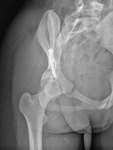

Bækken (dysplasi, postoperativt fra O-amb.)

AP

Lejring:

Stående AP (eller liggende) med benene 15° indadroteret.

Rørkipning:

0°.

Centrering:

Ca. 3 fingersbredder kranielt for symfysen.

Kriterier:

Led og skruer skal fremstilles. Ledspalten skal være tydeligt fremstillet. Det skal ALTID fremgå af billedet om det er taget stående eller liggende.